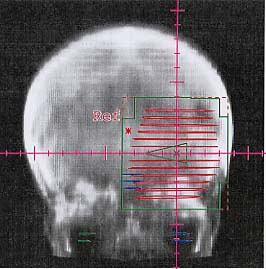

Hirntumore: Bestrahlungsplan

Bestrahlungspläne